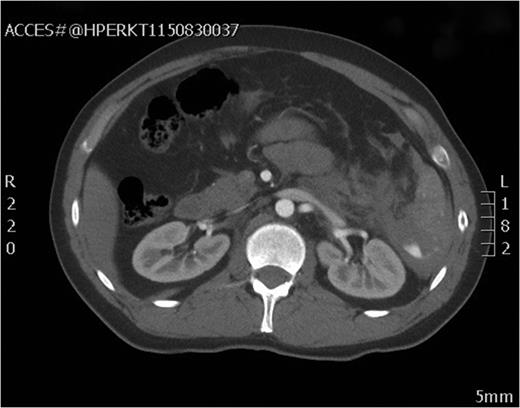

After the secondary survey, the patient was subjected to a computed tomography (CT) study, which showed a Grade IV splenic injury per the American Association for the Surgery of Trauma injury grading score with contrast extravasation (Fig. 1), a lower lobe contusion of the left lung, fractures of the IV and VI–XI ribs on the left side and bilateral iliac wing fractures. The pancreatic parenchyma was well perfused and homogenous in a portal venous phase CT-imaging (Fig. 2).

Axial view of the initial CT scan depicting a normally perfused pancreatic tissue.